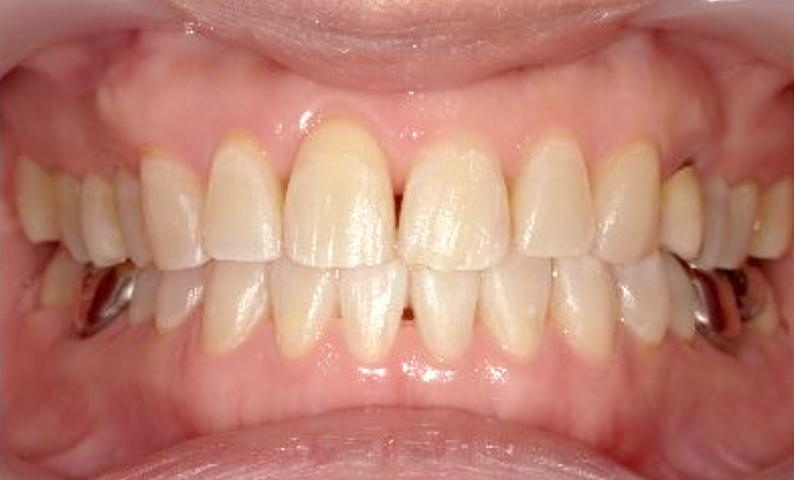

症例_003 下顎だけの部分矯正

治療期間:10ヶ月金額:24万円+税女性前歯のガタガタ下の前歯だけ上顎は補綴治療中

| Before | After |